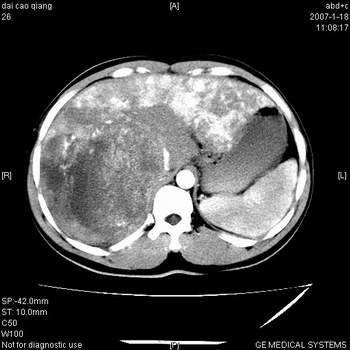

符合巨块型肝癌表现:

1、平扫低密度,增强后表现为快进快出。

2、动脉期可见迂曲的动脉供血血管

3、并可见门静脉右支癌栓形成

4、可见假包膜

5、腹主动脉旁结节影,考虑肿大淋巴结。

典型的肝右叶巨块型肝癌破裂、门脉瘤栓形成。

肝右叶巨大不均匀低密度肿块,前缘有假包膜,增强明显的呈快进快出表现,门脉右支有癌栓,病人虽然年轻但还是首先考虑肝右叶巨块形肝癌,病人血象高只能说有合并感染。不支持肝脓肿。

巨块型肝癌并门静脉右支癌栓

肝右叶巨块型肝癌破裂、门脉瘤栓形成。